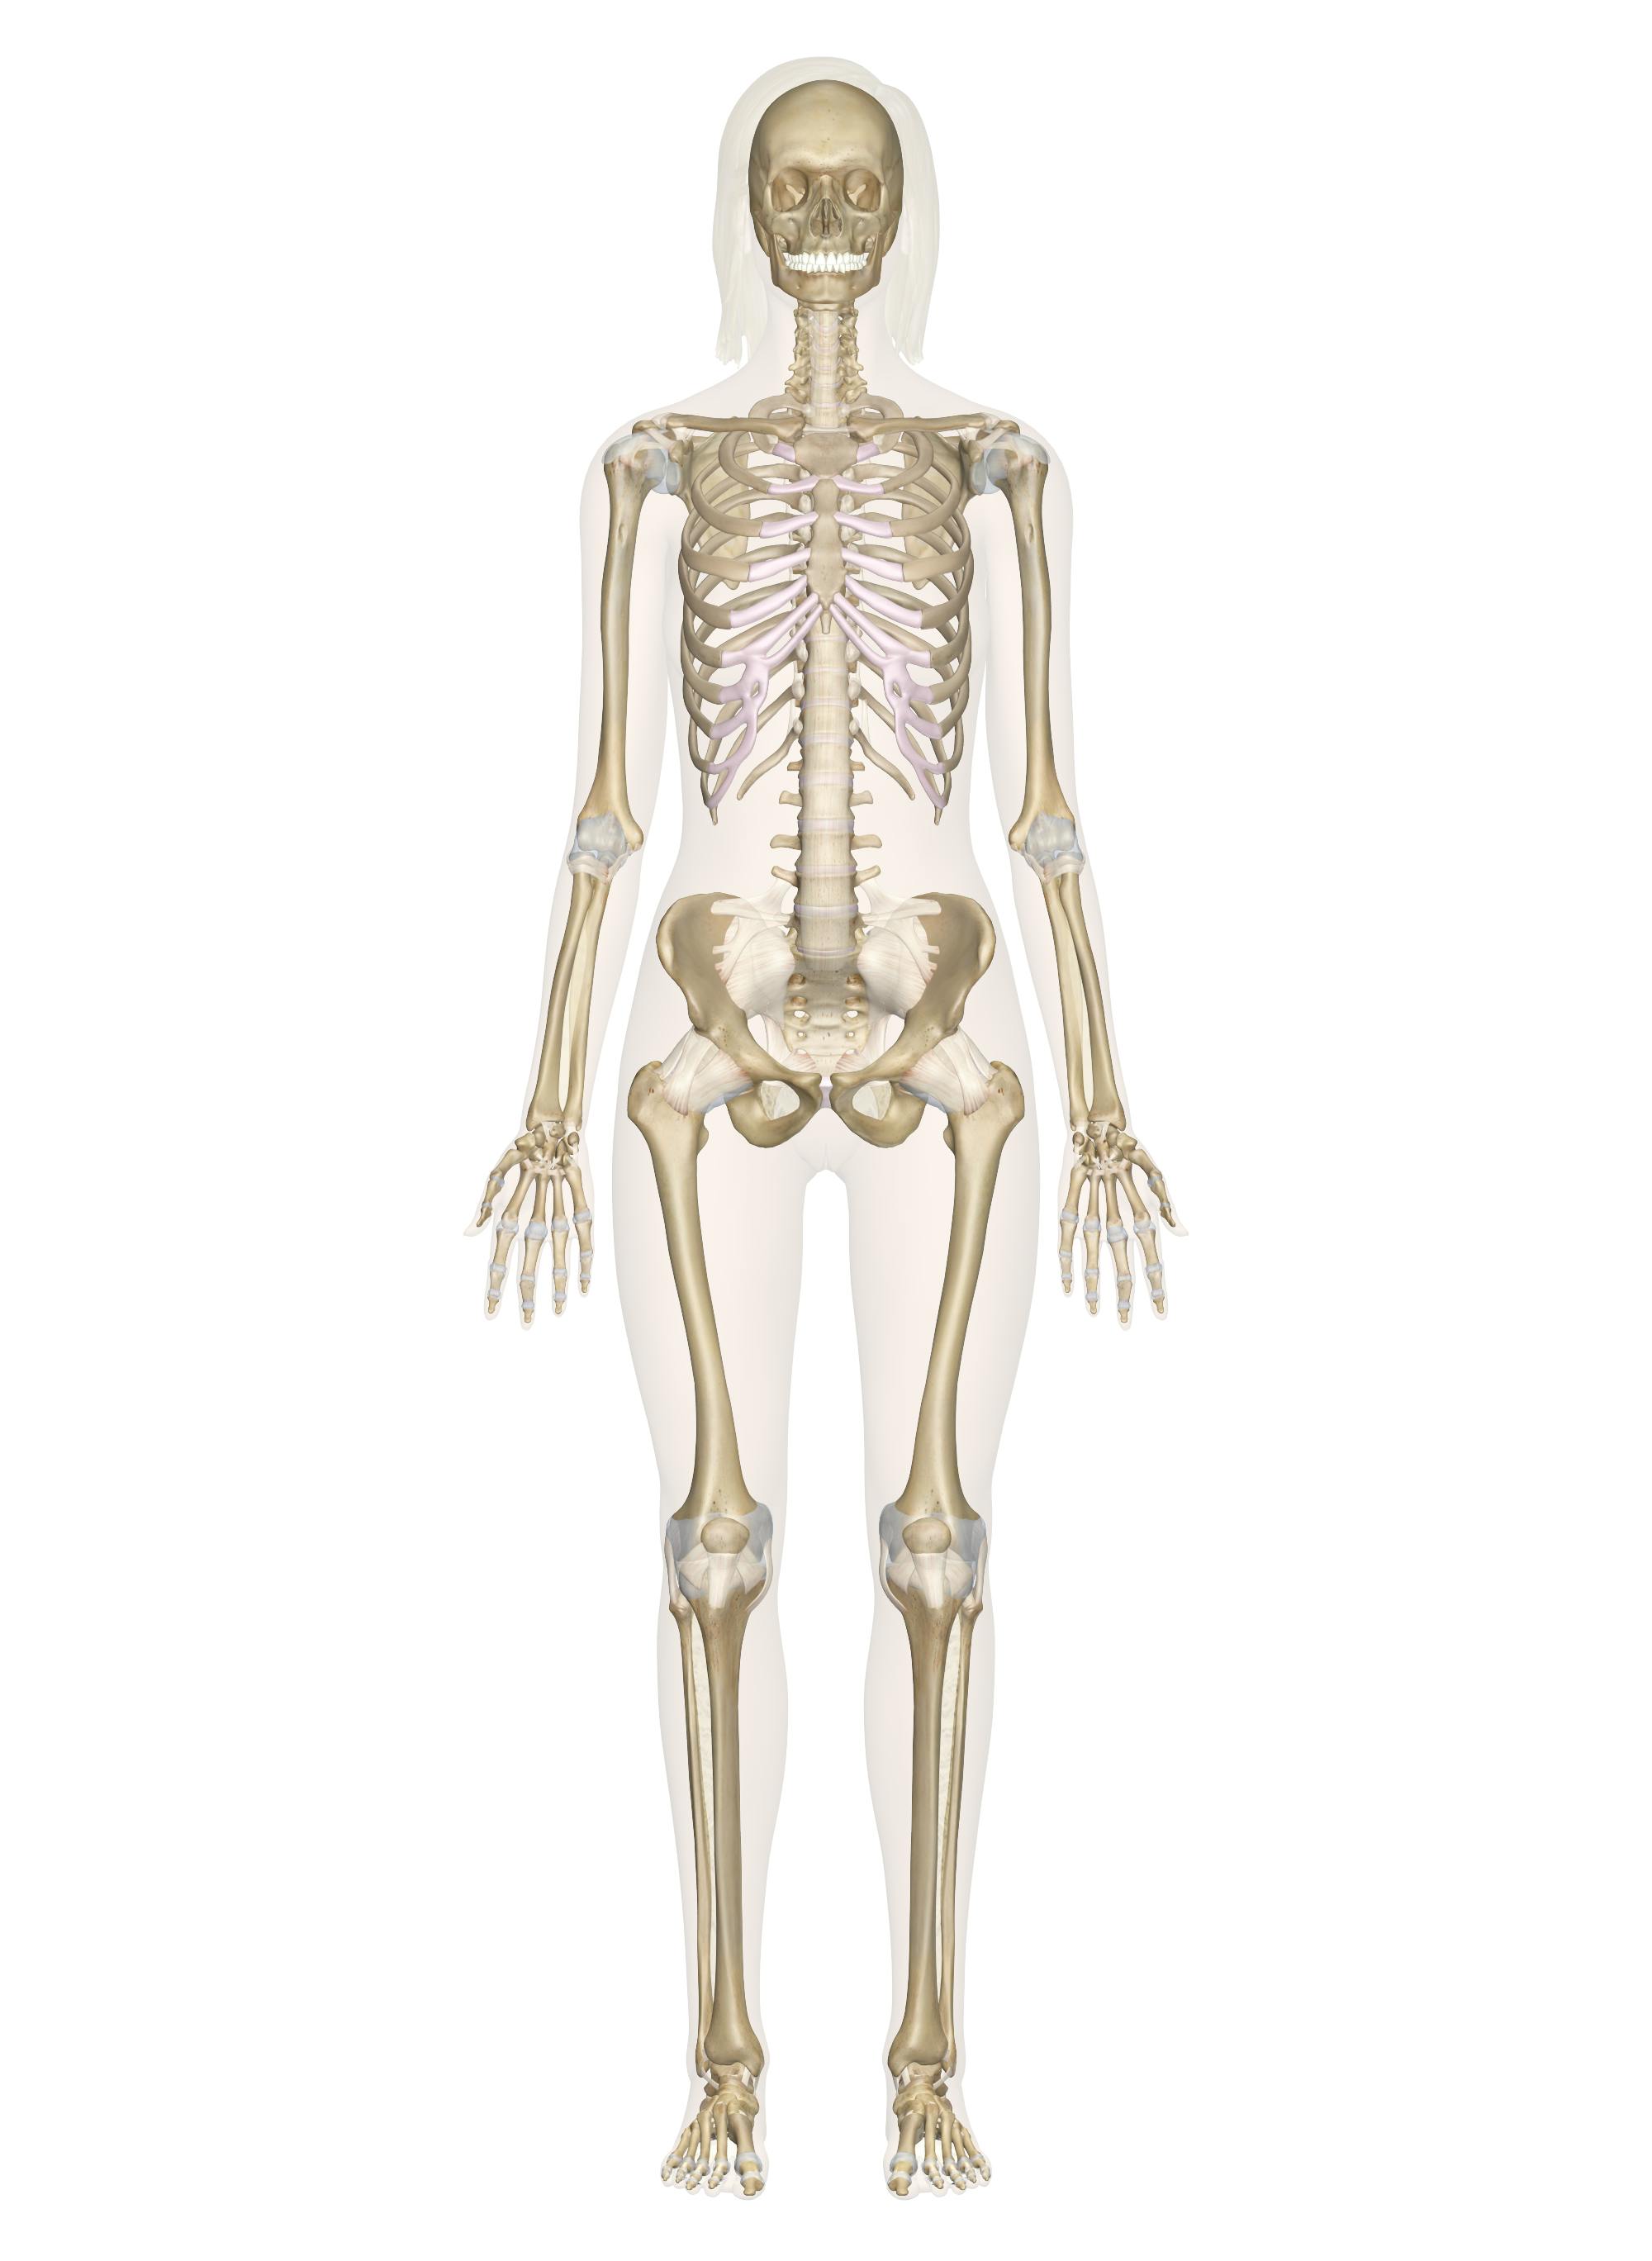

Diagram Of A Human Skeleton Human Hand Diagram

'human skeleton anatomy anatomical chart poster print' posters All of the following are functions of the skeleton except: Human skeletal drawing skeleton system anterior posterior diagram anatomy drawings

Human Skeletal System Diagram - coordstudenti

Skeleton human diagram blank bones printable chart unlabeled labeled phalanges skull thorax sternum carpus scapula clavicle radius mentioned humerus mandible Human skeletal system diagram Human hand diagram

Skeletal system human anatomy skeleton diagram chart structure labeled sketch bones picture body model labels structural locomotion posture adapted bipedalSkeletal system anatomy human labeled anatomical chart body bone physiology every organ health complex made Skeleton bones parts oseo humano esqueleto umano sparks anteriore posteriore spiegazioni scheletro delantero sportyHuman diagram skeletal system skeleton bones detailed diagrams skull.

The skeletal system anatomySkeleton chart Skeletal system human anatomy skeleton diagram chart labeled structure sketch picture bones body labels model bipedal locomotion adapted posture structuralHuman skeletal system diagram.

Human skeleton diagram stock photoImages 04. skeletal system Studia lavanda caricare human body anatomy bone structure tampone sìPrintable human skeleton diagram – labeled, unlabeled, and blank.

Human skeleton anatomy anterior skeletal system figure basic 3a joint brooksidepressPalace learning skeletal system anatomical chart Printable human skeleton diagramSkeletal anatomy labeled anatomical physiology.

Printable human skeleton diagramSkeletal skeleton labeled diagrams framework Human skeleton for kidsThe skeletal system chart.

Printable Human Skeleton Diagram – Labeled, Unlabeled, and Blank

human-skeleton-diagram – Tim's Printables

File:Human skeleton diagram.png

The Human Skeleton: All You Need to Know

Human Skeletal System Diagram - coordstudenti